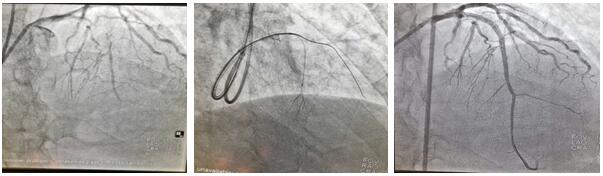

患者刘某某, 68岁男性,1月前于我院诊断:急性非ST段抬高型心肌梗死。行冠脉造影提示前降支近段100%闭塞,同侧穿膈支侧枝循环形成,回旋支近中段狭窄80%-90%,LAD为CTO病变,拟行完全血运重建治疗,顺利于回旋支病变处植入1枚支架,术中反复尝试各种导丝均未能开通LAD血管,历时近3小时,只能放弃,择期再处理。面对困难,面对失败,心血管二病区左梅主任医师团队,反复阅片,寻找失败原因,知难而上,勇于挑战,制订新的手术策略,决定为患者第二次开通LAD闭塞病变。在经过充分的术前讨论后于2020年7月2日第二次上台,由于患者LAD近段CTO病变,前次正向途径介入失败,右冠无良好侧枝形成,无逆向条件,拟行乒乓技术同侧微导管造影显示闭塞远段,提供正向导丝的指引,进入远端血管真腔;若失败,微导管跟进至血管内膜下,采用ADR(正向内膜下重回真腔)技术完成手术。手术的重要点在于控制血肿的大小。术中采用同侧双指引导管至左冠脉开口(乒乓技术),在一侧指引导管送微导管至穿膈支中段,超选择造影清晰显示LAD-CTO远段,另一侧指引导管内反复调试FieldXT-A导丝顺利通过闭塞病变至远段,在助手及导管室工作人员的全力配合下,历时不到1小时,成功完成手术。术中患者无任何不适及并发症发生,一家人很是欣喜。